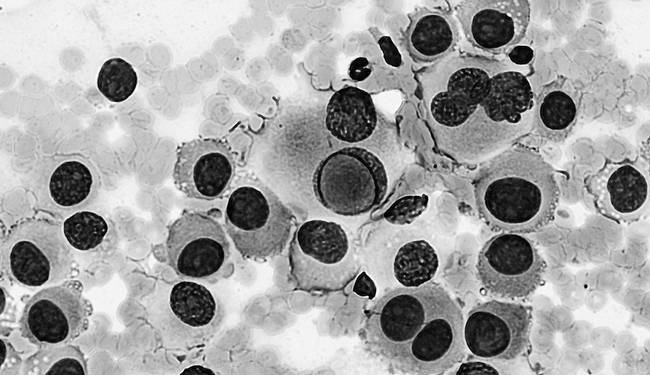

Паразитические черви Паразитические черви или гельминты – это плоские или круглые черви, чьих взрослых особей можно увидеть невооруженным глазом. Чаще всего гельминты живут в кишечнике и всасывают питательные вещества всей поверхностью своего тела. Они способны выживать в теле человека и животных в течение нескольких лет, поскольку обладают довольно прочными покровами, которые с трудом поддаются разрушению, а удерживаются в организме паразиты за счет множества приспособлений – крючков, липучек и присосок. Паразитические черви живут в организме благодаря тому, что они способны манипулировать иммунным ответом – выделять иммуномодулирующие вещества. Например, круглые черви филярии заставляют клетки иммунитета производить в 10 раз больше противовоспалительного цитокина IL-10, снижая эффективность иммунного ответа. Кроме того, они способны сокращать производство провоспалительных сигнальных молекул. Многие паразитические черви «обманывают» иммунитет и продолжают свое существование в организме человека, используя его ресурсы. ![]() Паразитический червь Filaria sp Все гельминты имеют сложный жизненный цикл, включающий в себя несколько стадий развития со сменой хозяина. Размножаясь, они откладывают яйца, которые защищают зародышей от неблагоприятных воздействий окружающей среды. В таком виде зародыши могут выживать вне организма хозяина несколько месяцев или даже лет. Пребывание паразитических организмов в теле человека может вызывать тяжелые последствия для его здоровья. Однако смерть организма-хозяина этим инфекционным агентам не выгодна. Именно благодаря способности гельминтов синтезировать вещества, которые регулируют иммунный ответ, самих паразитических червей иногда используют для лечения аутоиммунных и аллергических заболеваний, при которых иммунитет реагирует чрезмерно. Например, круглый червь власоглав способен вылечить аутовоспаление кишечника – болезнь Крона. Паразит вырабатывает вещества, которые способствуют синтезу противовоспалительных цитокинов. В результате организму удается избежать разрушительных последствий избыточной активации иммунной системы, которая вызывает сильное аутовоспаление в кишечнике. Наш иммунитет по-разному реагирует на различные внешние угрозы. Например, зараженные вирусом клетки организма уничтожаются Т-киллерами и натуральными киллерами, а клетки бактерий поглощаются в основном фагоцитами. Все эти упомянутые выше клетки эффективно борются с возбудителями грибковых инфекций, тогда как простейших и паразитических червей в первую очередь атакуют эозинофилы. Не будем забывать и о молекулярном компоненте защиты. Антитела помогают распознавать чужеродные болезнетворные агенты, которые связались с клетками или частицами патогенов, а антимикробные белки и пептиды способны убивать патогены напрямую. Умершие клетки или «клеточный мусор» В организме постоянно гибнут клетки, которые в результате становятся клеточным «мусором». Его накопление чревато возникновением аутоиммунных заболеваний – воспалительных процессов, при которых здоровые клетки организма и их части воспринимаются иммунитетом как нечто чужеродное и опасное. Если распознавание осуществилось, запускается выработка антител, действие которых направлено против собственных белков, клеток и их частей. В подобных ситуациях антитела – главным образом IgM, IgG – сигнализируют иммунным клеткам об опасности и необходимости уничтожить потенциальную опасность. Они связываются с «клеточными отходами», маркируют их, образуя при этом иммунные комплексы. В результате в организме присутствуют антитела, связанные с антигенами, в роли которых выступают «свои» же белки, клетки и их фрагменты. С этими комплексами взаимодействуют иммунные клетки – макрофаги, нейтрофилы, тучные клетки, базофилы. Они попадают в очаг реакции, связываются с этими антителами и запускают процесс воспаления. Во многом благодаря сериалу «Доктор Хаус», одним из самых известных аутоиммунных заболеваний стала системная красная волчанка. Ее возникновение может быть вызвано накоплением «клеточного мусора». К сожалению, системная красная волчанка – одно из многих аутоиммунных заболеваний. Среди них – ревматоидный артрит, атипичный гемолитико-уремический синдром, наследственная ангиоэдема, болезнь Крона, сахарный диабет I-го типа, аутоиммунная гемолитическая анемия, рассеянный склероз и многие другие. Все аутоиммунные заболевания до сих пор неизлечимы. ![]() Виды клеточной гибели: апоптоз и некроз Когда клетки организма выходят из строя или погибают, в межклеточном пространстве появляются молекулы, которых в норме там быть не должно. Это своеобразный сигнал иммунной системе – она фиксирует такие сбои и удаляет мертвые клетки из организма. Удаление остатков клеток из организма происходит без воспалительных процессов, то есть с минимальными затратами для организма. Опухолевые клетки Раковые клетки или опухолевые клетки – это дефектные клетки-мутанты, которые не могут больше выполнять свои функции в тканях и органах. Раковые клетки опасны для организма человека, потому что они бесконтрольно размножаются, поглощают питательные вещества, необходимые для здоровых клеток, тканей и органов и не выполняют специализированных функций. Кроме того, опухолевые клетки могут распространяться по всему организму и вызывать опухоли в теле, то есть метастазировать. Это может приводить к отказу работы органов и смерти человека. Для того, чтобы опухоль не смогла образоваться и развиться, иммунитет находит злокачественные клетки и уничтожает их на самых ранних этапах. ![]() Меланома. Клетки рака кожи К сожалению, иммунная система не всегда может обнаружить и уничтожить опухолевые клетки – многие из них обладают набором свойств, которые позволяют избежать распознавания со стороны иммунитета. Если это происходит, раковые клетки продолжают бесконтрольно расти и размножаться. В некоторых случаях иммунная система начинает борьбу с опухолью, но все ее реакции лишь провоцируют рост числа раковых клеток и осложняют течение заболевания. Почему так происходит? Ответ на этот вопрос наука не знает до сих пор. В наши дни активно развиваются несколько способов борьбы с раком. В том числе – иммунотерапия. Этот вид лечения подразумевает активацию или подавление нашего собственного иммунитета для борьбы с опухолями. В качестве терапевтических агентов часто используются антитела, способные распознавать опухолевые антигены. Они помогают клеткам иммунитета обнаруживать мишени и запускать в их отношении иммунный ответ. Помимо этого, для мобилизации иммунитета и действия против клеток злокачественных опухолей используют сигнальные молекулы – интерфероны и интерлейкины, привлекающие иммунные клетки в очаг опухоли, а также NK-клетки (натуральные киллеры) и T-киллеры, которые непосредственно уничтожают раковые клетки. |